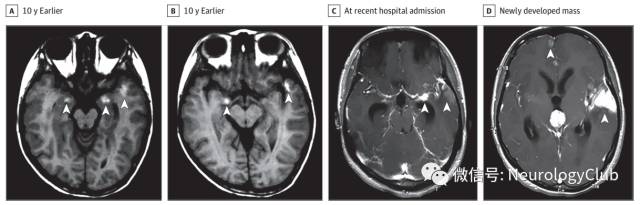

一中国青年女性,因间歇性跛行和逐渐加重的头痛入院。患者10年前开始出现间歇性跛行。当时的头颅MRI提示多发脑实质病灶,累及脑桥,双侧杏仁核和左侧颞极(图A)。患者拒绝进一步检查直到1年前出现轻度头痛。MRI可见左侧颞极病灶局部轻微增大。1月前,患者头痛加重,难以忍受。增强MRI可见左侧颞叶病灶明显进展,累及颞极和大脑侧裂旁区域,三脑室出现新发肿块伴梗阻性脑积水。脑桥和右侧杏仁核病灶基本同前(图B)。脊髓MRI正常。无其他部位肿瘤病史。家族史无殊。患者意识清,但记忆力和注意力下降。瞳孔反射正常。全身可见多发先天性色素痣,腿部2处,直径大于5cm,背部和面部3处,直径大于3cm。未见局灶性运动障碍和感觉缺失。反射正常。余查体无殊。

(图:A-B:10年前的T1WI可见脑桥、双侧杏仁核和左侧颞极多发脑实质病灶;C-D:增强T1可见左侧颞叶病灶明显进展,累及颞极和大脑侧裂旁区域,三脑室出现新发肿块伴梗阻性脑积水

本例患者有趣之处在于其10年病程,是目前已知生存期最长的NM患者。从中可以看到颅内NM的演变过程,不同于先前描述的从脑膜黑色素细胞瘤过渡为原发脑实质黑色素细胞瘤。左侧颞叶病灶的进展及三脑室病灶的出现提示肿瘤具有异质性且有恶变潜能。后者导致脑积水,病理提示高度恶性,Ki-67指数大于60%。